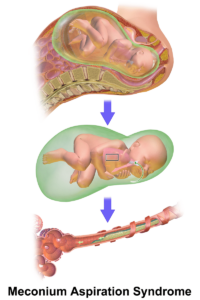

Maternal-Newborn Nursing

Cheatsheets

71

Mnemonics

24

Images

86

Picmonic

0